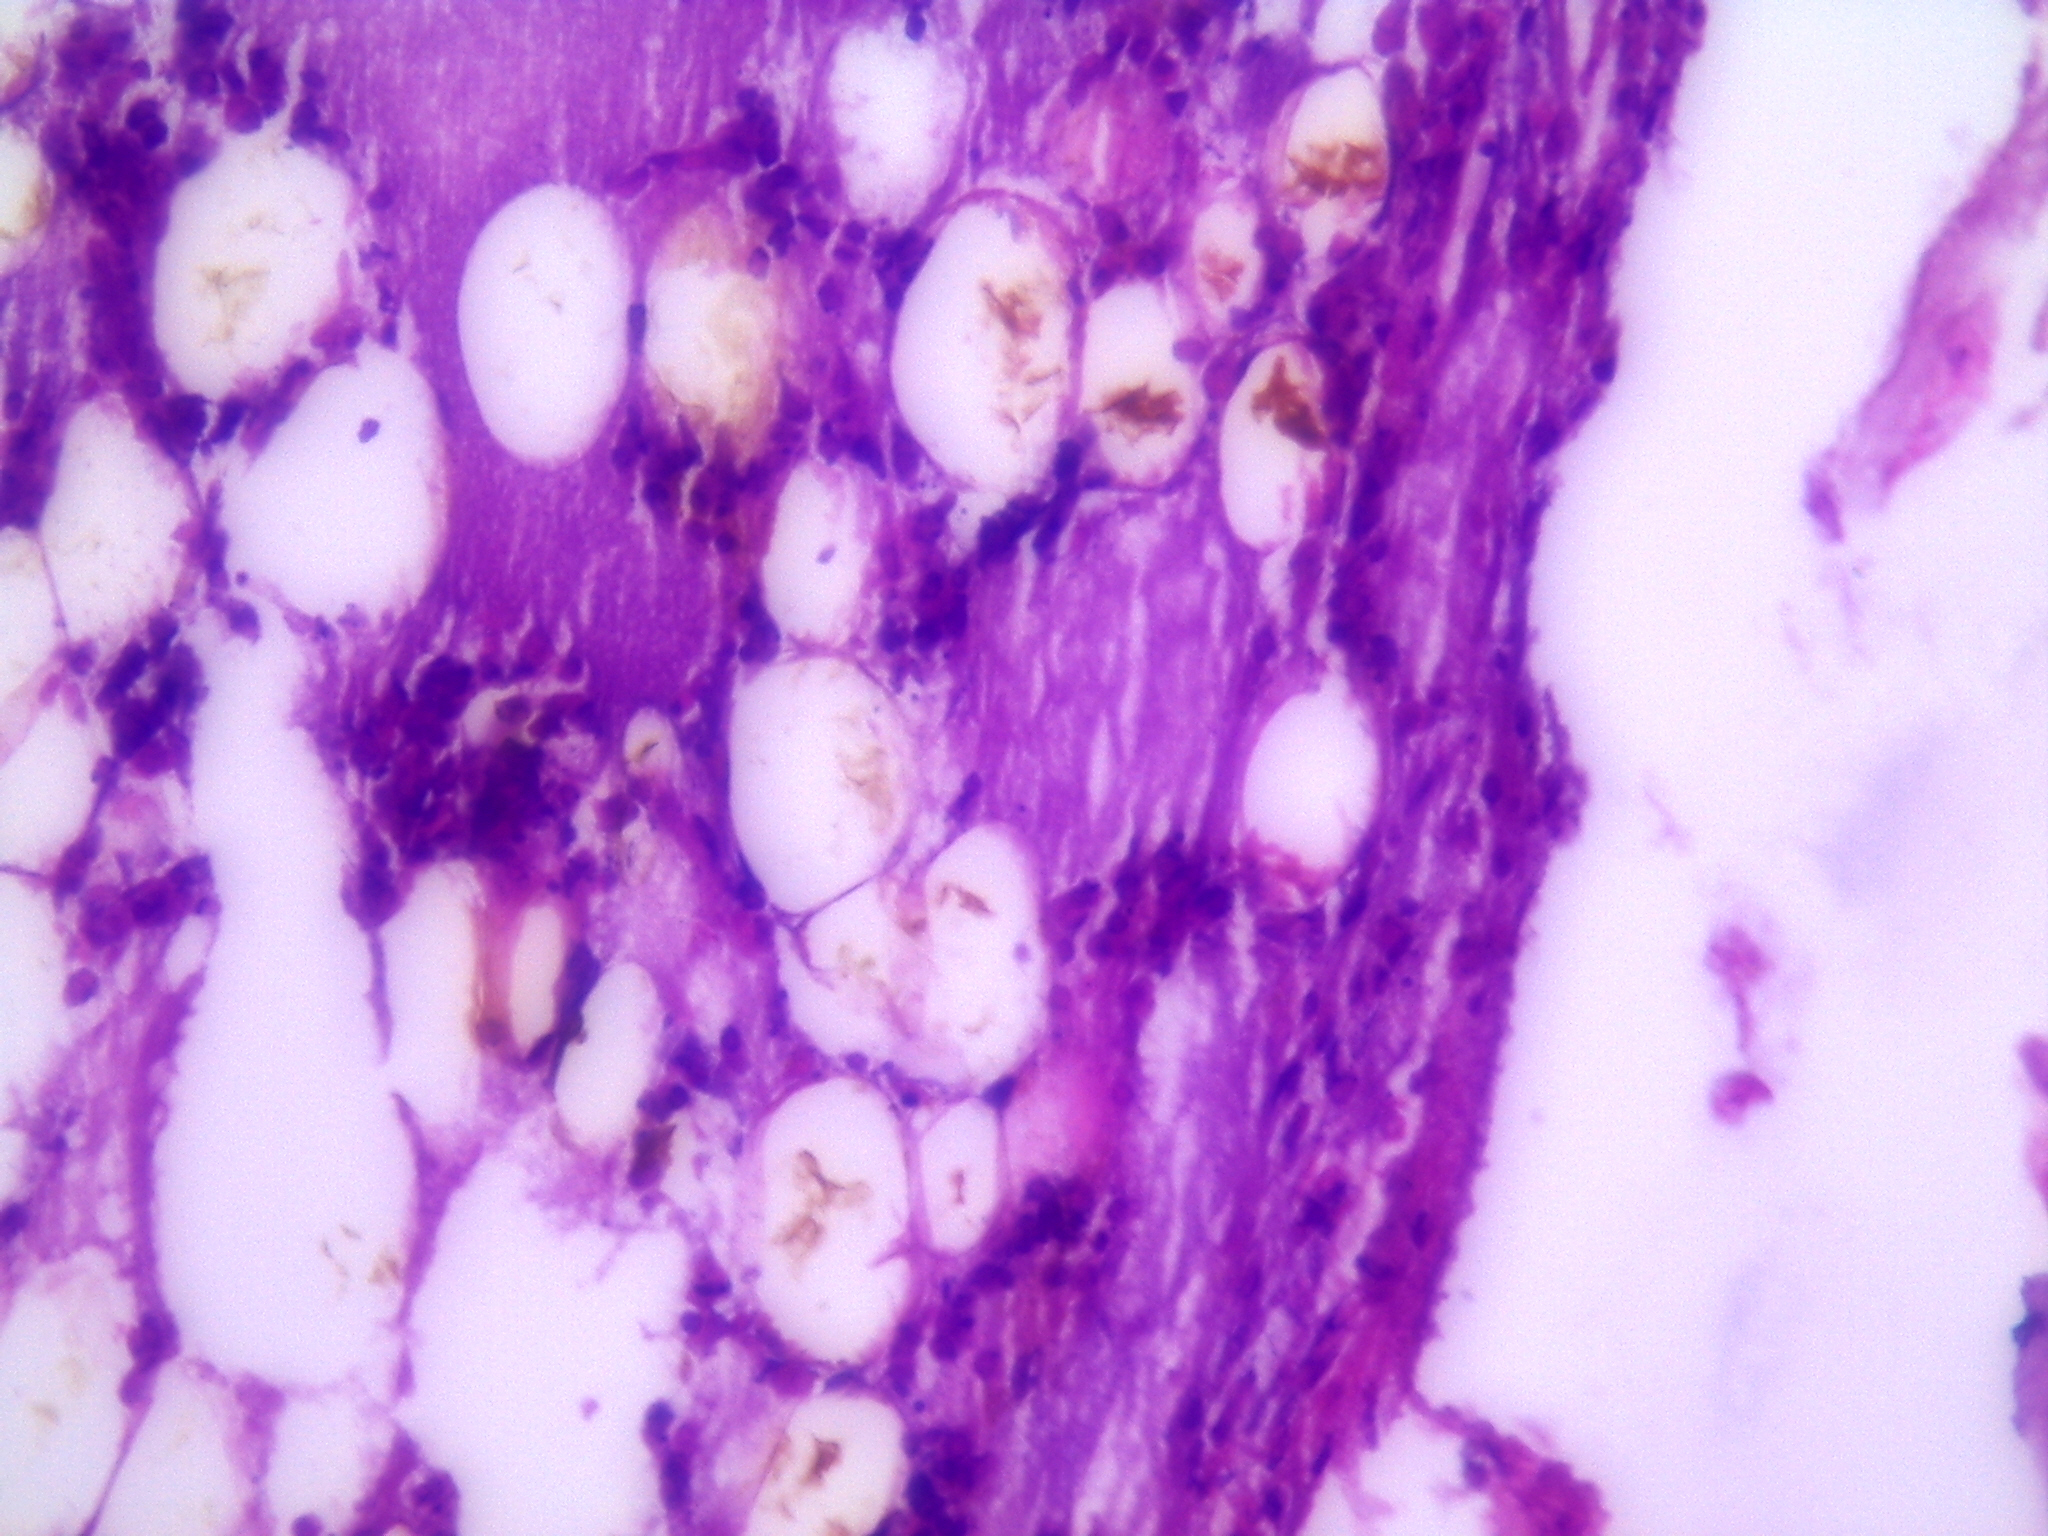

IntroducciónEl objetivo de este estudio experimental fue evaluar el resultado radiológico e histológico de la utilización de alendronato colocado localmente en el foco de fracturas de fémur en conejos.Material y métodosSe utilizaron 30 conejos a los cuales se fracturó el fémur derecho y se distribuyeron en tres grupos de 10 animales cada uno. A los conejos del grupo I se le colocó una solución con alendronato a nivel del foco de fractura, al grupo II se le realizó el mismo procedimiento a los siete días de la fractura, dejando el grupo III como control. Se realizó la evaluación radiográfica al momento de la fractura y a los 42 días del procedimiento. Se evaluó las características de callo óseo mediante anatomía patológica, radiología y tomografía axial computada.ResultadosSe evaluaron 24 conejos, por el fallecimiento de dos conejos del grupo II y cuatro del grupo III. El análisis histológico evidenció moderada formación ósea en los tres grupos sin diferencias estadísticamente significativas (p=0,8336). En cuanto a los resultados evaluados por estudios de imagen no existieron diferencias estadísticamente significativas del tamaño del callo óseo entre los grupos para los dos estudios (p= 0,777 en Rx y p=0,349 en TAC).ConclusiónLos resultados de este trabajo experimental evidenciaron que la utilización de alendronato colocado localmente en el foco de fractura no afectó de manera estadísticamente significativa, histológica ni radiológicamente, el proceso de consolidación en las primeras 6 semanas posteriores a la fractura de fémur en conejos. AbstractIntroduction: The aim of this experimental study was to evaluate the radiologic and histological results of the use of alendronate administered locally at the fractures site in rabbits.Methods: The fractured right femur of 30 rabbits was used for evaluation. The animals were distributed in three groups of 10 rabbits each. A solution with alendronate was placed at the fracture site in group 1; the same procedure was performed 7 days after the fracture in group 2, and group 3 functioned as control. Radiographic evaluation was performed at the time of the fracture and at day 42. Radiological, PA and CT-scan evaluations of bone callus characteristics in each rabbit were performed.Results: Twenty-four rabbits were evaluated (2 rabbits in group 2 and 4 in group 3 died). Histological evaluation evidenced moderate bone formation in the three groups without statistically significant differences (p=0.8336). Concerning imaging studies, there were no statistically significant differences in the size of bone callus among groups for both studies (X-rays: p=0.777 and CT: p=0.349).Conclusion: The use of alendronate administered locally at the fracture site, in the acute period and after one week, did not alter the normal consolidation process determined by PA and radiology, six weeks after femur fracture in rabbits.Descargas